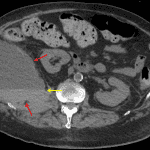

- Large, mixed density right retroperitoneal collection measuring 15 x 10 x 17 cm with a hematocrit level and surrounding fat stranding

- Thickening of the posterior limb of Gerota’s fascia on the right

- Anterior displacement of the right kidney with a subcentimeter hypodense structure in the anterior interpolar region, which is too small to characterize

- Right iliacus and left psoas intramuscular hematomas

- Retroperitoneal hematoma

Large acute right retroperitoneal hematoma which results in anterior displacement of the right kidney. Unable to assess for active hemorrhage in the absence of IV contrast material.

Smaller acute right iliacus and left psoas intramuscular hematomas.